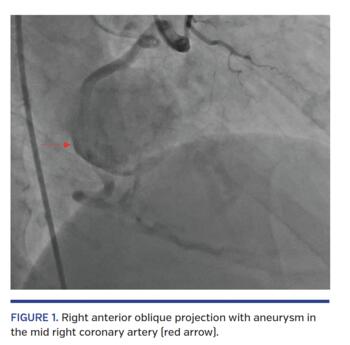

A 66-year-old male with end-stage renal disease presented with chest pain, dyspnea, and hypotension. Cardiac catheterization was negative for tamponade, but there was a large saccular aneurysm in the mid right coronary artery (Figure 1; Video 1). Saphenous vein coronary bypass graft was utilized by attaching the proximal end of the graft to the aorta and distal end to the right coronary artery distal to the aneurysm. The aneurysm was ligated to avoid risk of rupture.